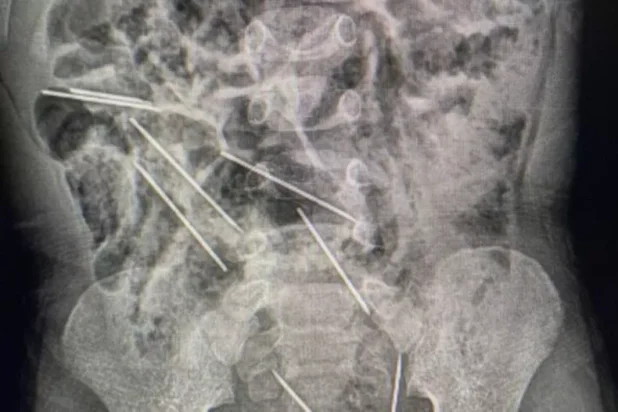

Οι γιατροί επαρχιακού νοσοκομείου στο βόρειο Περού, ξαφνιάστηκαν όταν είδαν την ακτινογραφία του λιλιπούτειου ασθενή που έφθασε στα επείγοντα από αγρόκτημα της περιοχής Ταρατόπο 622 χμ από την πρωτεύουσα Λίμα. Στο κορμί του δίχρονου παιδιού εντοπίστηκαν όχι μία και δύο, αλλά 8 μεγάλες βελόνες από αυτές που χρησιμοποιούνται για ενέσεις σε αγελάδες.

Δύο ώρες διήρκεσε η περίπλοκη και λεπτή επέμβαση για την αφαίρεσή τους. «Μόλις ανοίξαμε την κοιλιά διαπιστώσαμε ότι αυτά τα μεταλλικά σώματα ήταν βελόνες Νο. 21 για ενέσεις, κομμένες στην άκρη. Βρήκαμε δύο στη δεξιά πλευρά του περιτοναίου, μια άλλη στο επίπλουν (ιστός της κοιλιακής κοιλότητας) τρεις στην αριστερή πλευρά, μία στο κοιλιακό τοίχωμα και δύο που ήταν επικίνδυνα χαμηλά μεταξύ της ουροδόχου κύστης και του ορθού», δήλωσε ο γιατρός.